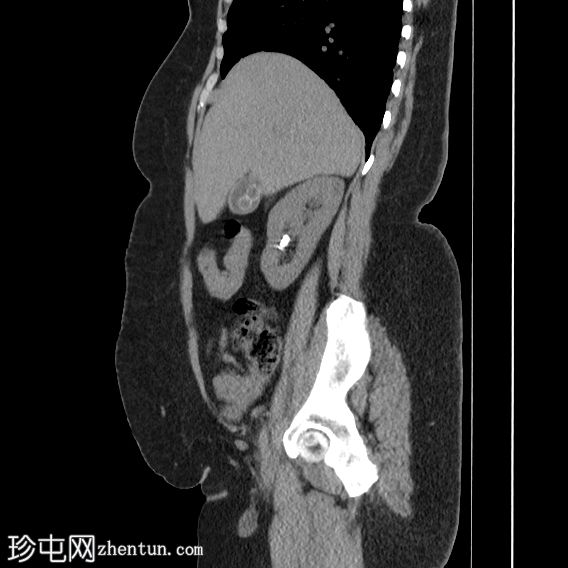

冠状位

平扫

胆囊内可见多发大小不一的多面环状钙化胆结石。胆总管直径处于正常上限。胆总管内未见其他结石。

右侧肾中盏可见一非梗阻性结石(10.5 mm),CT值较高(900–1000 HU)。